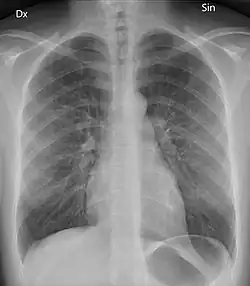

A normal posteroanterior (PA) chest radiograph of someone without any signs of injury. Dx and Sin stand for "right" and "left" respectively.